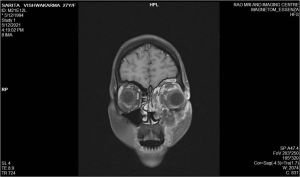

- Magnetic Resonance Imaging of the orbit and brain (with gadolinium contrast)